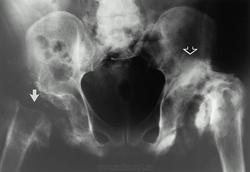

При табетической артропатии обычно поражается один, реже — два сустава. Наиболее часто страдают суставы нижней конечности — коленный и тазобедренный. При табетической артропатии тазобедренного сустава костные разрастания окружают кость, особенно с медиальной стороны. Обычны переломы шейки бедра и вертлужной впадины. Головка бедренной кости полностью рассасывается и кость укорачивается. В коленном суставе чаще наблюдается поперечный перелом над мыщелками бедренной кости или отрывается один из мыщелков. Костные разрастания очень пышные. Нередко развивается подвывих.

Артропатии при спинной сухотке.

14.rin_.slayd14.jpg15.rin_.slayd15.jpg16.rin_.slayd16.jpg17.rin_.slayd17_0.jpg